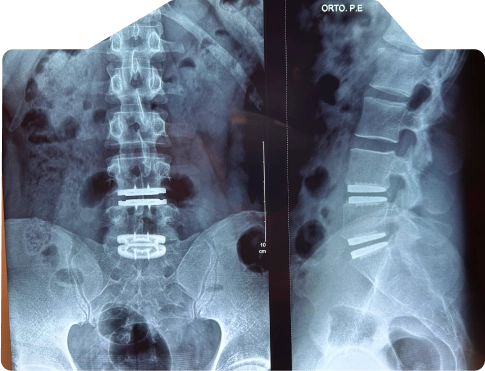

Veja casos de antes e depois dos meus pacientes:

A artrodese, também conhecida como fusão espinhal, é um procedimento cirúrgico que visa aliviar a dor. é feito a fusão de duas ou mais vértebras para estabilizar a coluna e aliviar a dor causada pelo movimento vertebral.